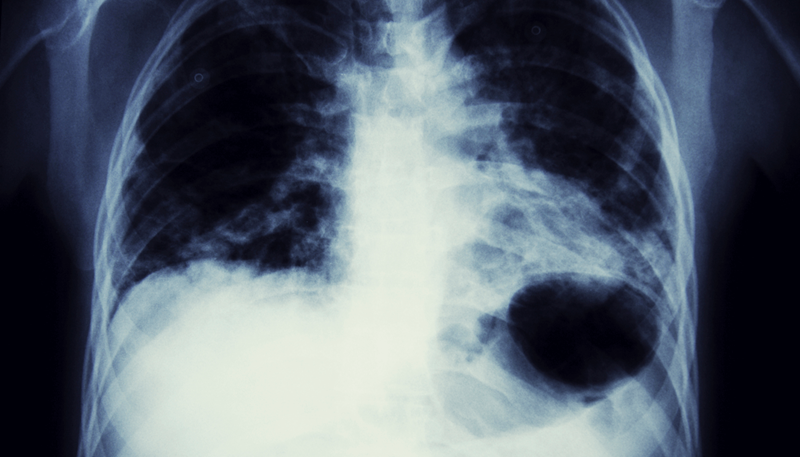

Pleural Thickening Claims

As well as supporting clients with pleural thickening claims, we also have experience in other types of asbestos-related disease claims, including:

• Lung cancer

• Asbestosis

• Mesothelioma